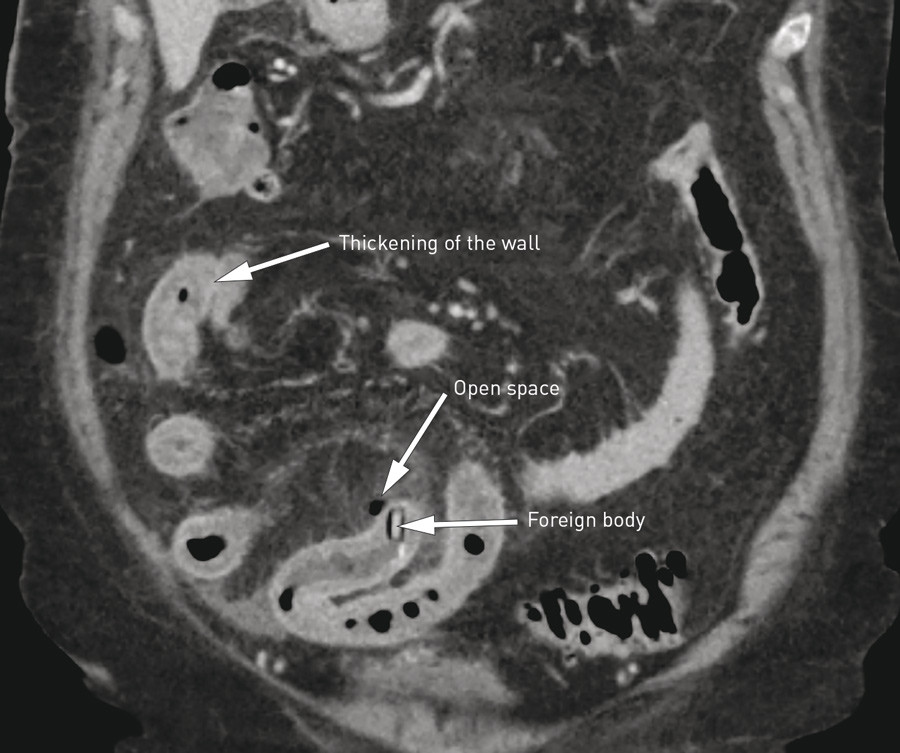

The patient was examined using laboratory tests, ECG and abdominal CT scan with intravenous contrast medium. The laboratory values on admission revealed elevated inflammatory markers, but otherwise normal values: Hb 11.5 g/l (11.4 – 15.3 g/l), leukocytes 19.5 · 10⁹l (3.5 – 8.8 · 10⁹l), CRP 210 mg/l (< 5 mg/l), Na 139 mmol/l (137 – 145 mmol/l), K 4.5 mmol/l (3.6 – 5.0 mmol/l), creatinine 87 μmol/l (56 – 110 μmol/l), amylase 21 U/l (10 – 60 U/l, bilirubin 18 μmol/l (< 25 μmol/l), alaninaminotransferase (ALAT) 22 U/l (10 – 45 U/l), alkaline phosphatase (ALP) 82 U/l (35 – 105 U/l). ECG showed sinus rhythm with no signs of ischaemia. Abdominal CT scan with contrast medium showed normal basal pulmonary cross-section. Signs were observed in the abdomen of local inflammatory changes in the small intestine with a space outside the gastrointestinal wall related to a foreign body in the intestinal lumen (Fig.1).

Figure 1  Abdominal CT scan shows perforation of the small intestine by a foreign body (tablet in blister pack) and…

Figure 1 Abdominal CT scan shows perforation of the small intestine by a foreign body (tablet in blister pack) and thickening/oedema of the intestinal wall orally to the foreign body